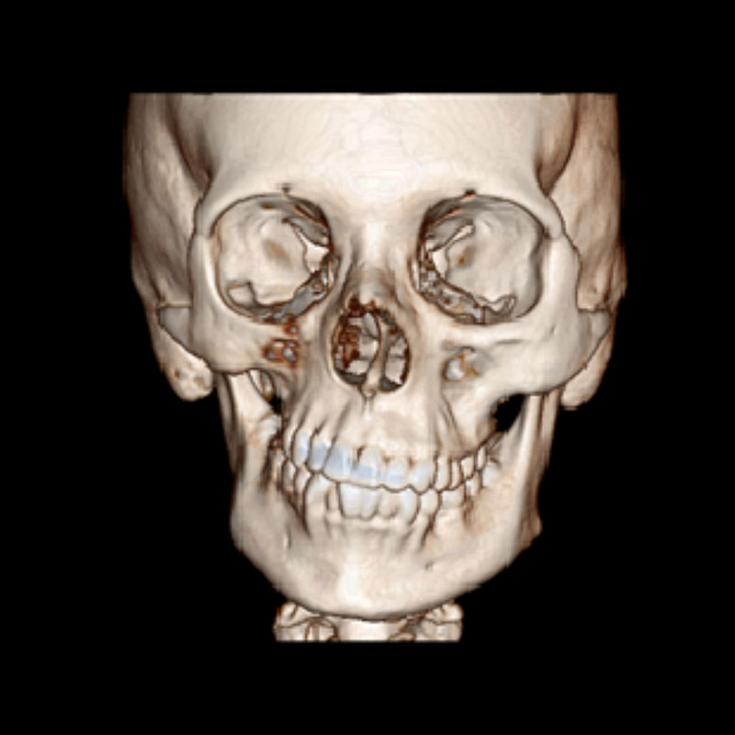

The disease progressively spreads from the zygomatic bone region, resulting in atrophy of the skin and its appendages, as well as underlying subcutaneous structures such as connective tissue (fat, fascia, cartilage, bone) and/or muscles on one side of the face. The mouth and nose usually deviate towards the affected side of the face.

The process may eventually spread to tissues between the nose and upper lip angle, upper jaw, corner of the mouth, eye and brow area, ear and/or neck.

Diagnosis of progressive hemiatrophy of the face

Diagnosis can be made solely on the basis of the history and physical examination of people who have only facial asymmetry. For those reporting neurological symptoms such as migraine or seizures, brain MRI is the imaging modality of choice. Diagnostic lumbar puncture and serum autoantibody testing may also be indicated. Oligoclonal bands and an elevated IgG index can be detected in 50% of patients.